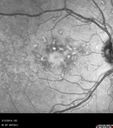

45 year old man was told to come in because of ‘white spots on their retina’. He now has to take his glasses off to read labels. He has always had trouble with oncoming headlights messing up his vision for a short time. VA OD: cc20/20 NscJ1 OS: cc20/20 NscJ1+ Pisciform lesions in the macula of both eyes.

Fundus Flavimaculatus - Asymptomatic - Color Photo749 views45 year old man was told to come in because of ‘white spots on their retina’.